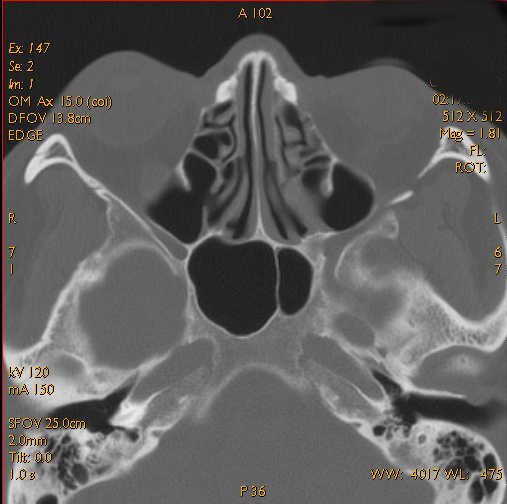

What are the normal characteristics of sinuses? Click the image for labeling.